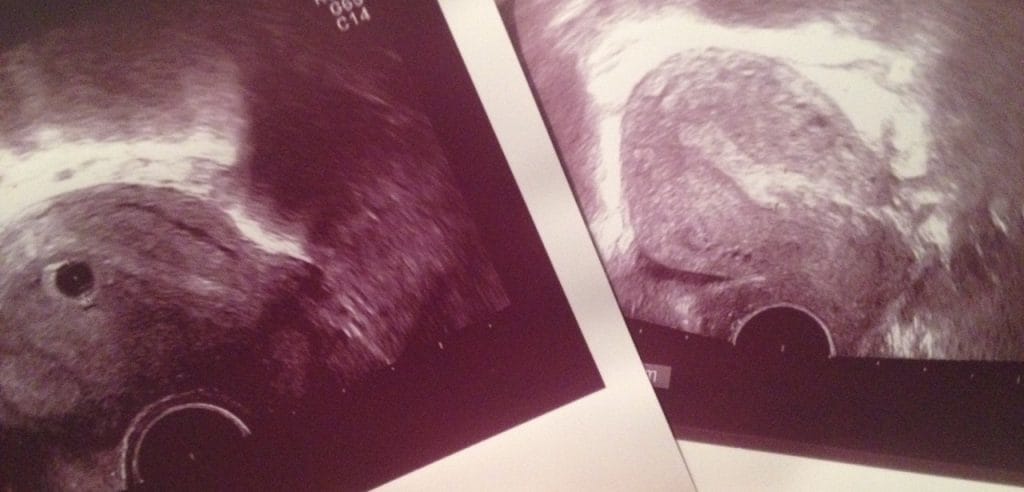

Ultrazvok

V petek na prvem pregledu smo opravili tudi prvi ultrazvok, mož je šel z menoj in oba sva komaj čakala na to kar sva mislila, da bova videla. Videla pa sva veliko manj. To kar je bilo na ekranu, je bilo očitno nepričakovano tudi za zdravnico, ki mi je takoj razložila, da se vrečka vidi, kaj več pa (še) ne. Predvidevali smo, da gre za pozno zanositev. Dobila sem datum novega pregleda čez 14 dni in takrat naj bi preverili napredek. Izpolnili smo materinsko knjižico in precej dobre volje sem se odpravila do laboratorija da uredimo še ostalo in nato je sledil kar precej pester dan.